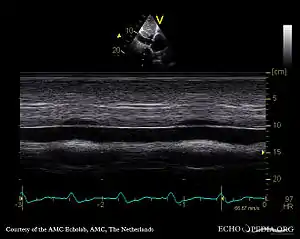

Echocardiography

If pulmonary hypertension is suspected based on the above assessments, echocardiography is performed as the next step.[12][14][55] A meta-analysis of Doppler echocardiography for predicting the results of right heart catheterization reported a sensitivity and specificity of 88% and 56%, respectively.[57] Thus, Doppler echocardiography can suggest the presence of pulmonary hypertension, but right heart catheterization (described below) remains the gold standard for diagnosis of PAH.[12][14] Echocardiography can also help to detect congenital heart disease as a cause of pulmonary hypertension.[12]

- 4-month-old with pulmonary hypertension as seen on ultrasound[58]

4-month-old with pulmonary hypertension as seen on ultrasound[58]- Long standing pulmonary hypertension[59]